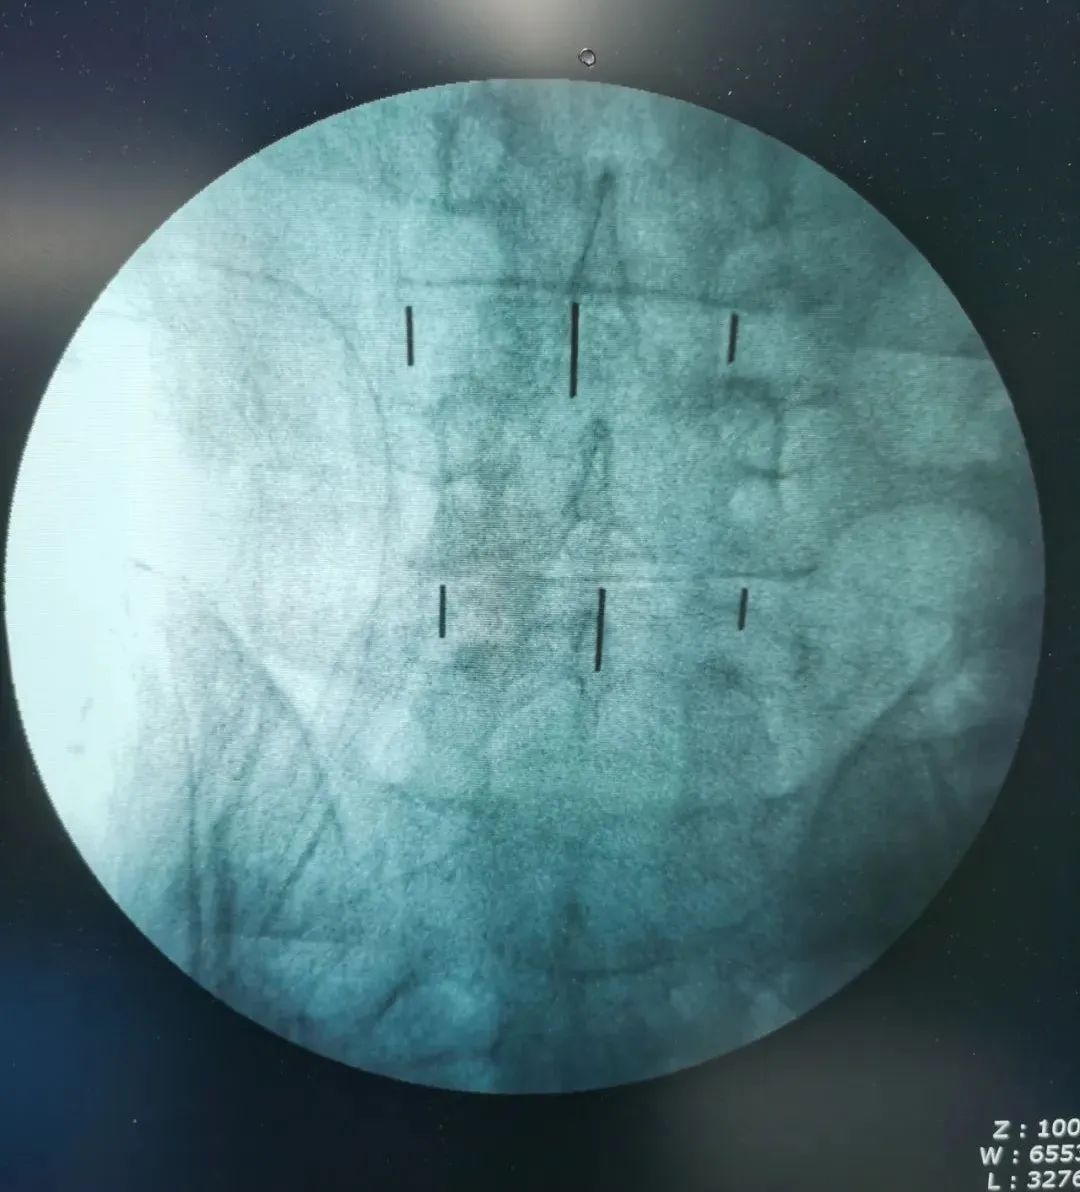

▲标记

▲术中影像

经过周密细致地术前讨论及评估,由张少华主任主刀,熊东医生、手术室(麻醉科)默契配合,为李先生成功实施“OLIF腰椎微创椎体间融合术”,目的:减压,复位,融合;术中操作干净利落、精准微创,顺利完成,手术历时近4小时。